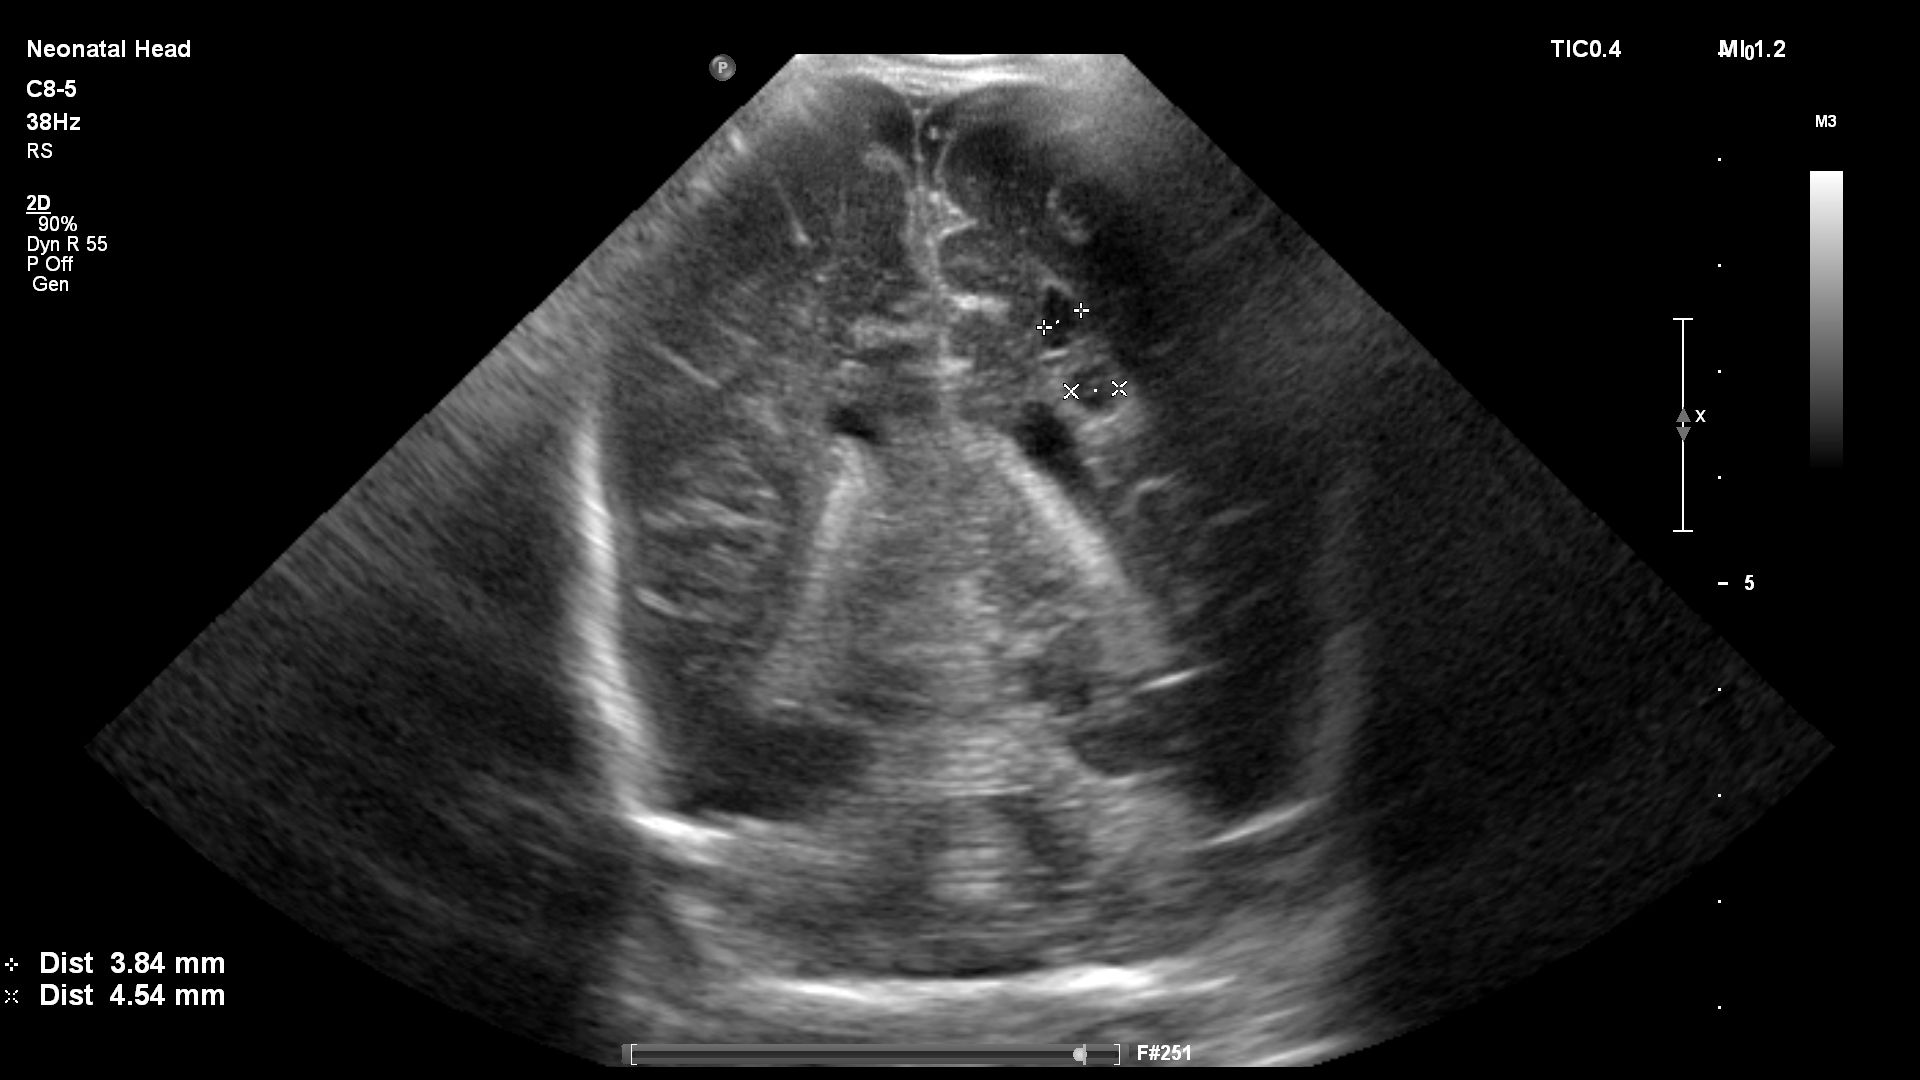

Preterm premature rupture of membranes (pPROM) before 22–24 weeks of gestation is considered previable and poses a high risk to the chances of successful delivery. Multicystic dysplastic kidney (MCDK) is the most common form of dysplasia of this organ, usually affecting 1 kidney. A prenatal suspicion of MCDK requires escalation of the clinical process to a reference center qualified and equipped for further diagnosis and treatment. We present a unique case of prenatal pPROM at 19 weeks of gestation in a pregnancy complicated by fetal MCDK as an interesting obstetric and neonatal patient story. We have not found any published evidence on the impact of coexisting fetal congenital malformations on a pregnancy affected by previable pPROM.

Agut T, Alarcon A, Cabañas F, Bartocci M, Martinez-Biarge M, Horsch S, et al. Preterm white matter injury: ultrasound diagnosis and classification. Pediatr Res 2020;87(Suppl 1):37-49.

Balasundaram M, Chock VY, Wu HY, Blumenfeld YJ, Hintz SR. Predictors of poor neonatal outcomes in prenatally diagnosed multicystic dysplastic kidney disease. J Perinatol 2018;38(6):658-64.